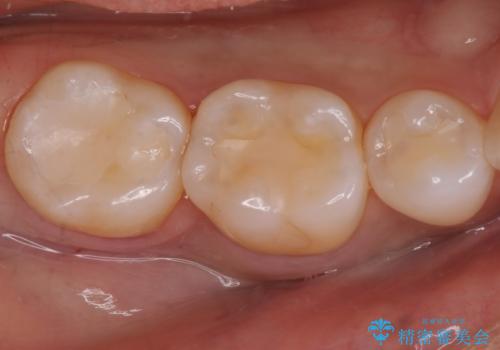

奥歯が欠けた セラミックインレーでの修復後、ナイトガード装着

欠けた部分にはセラミックインレーで修復処置を行い、今後の破折リスクを抑えるためにナイトガードを製作していきます。

- 右下7 セラミックインレー 77,000円/ナイトガード 33,000円費用は治療当時の料金となります